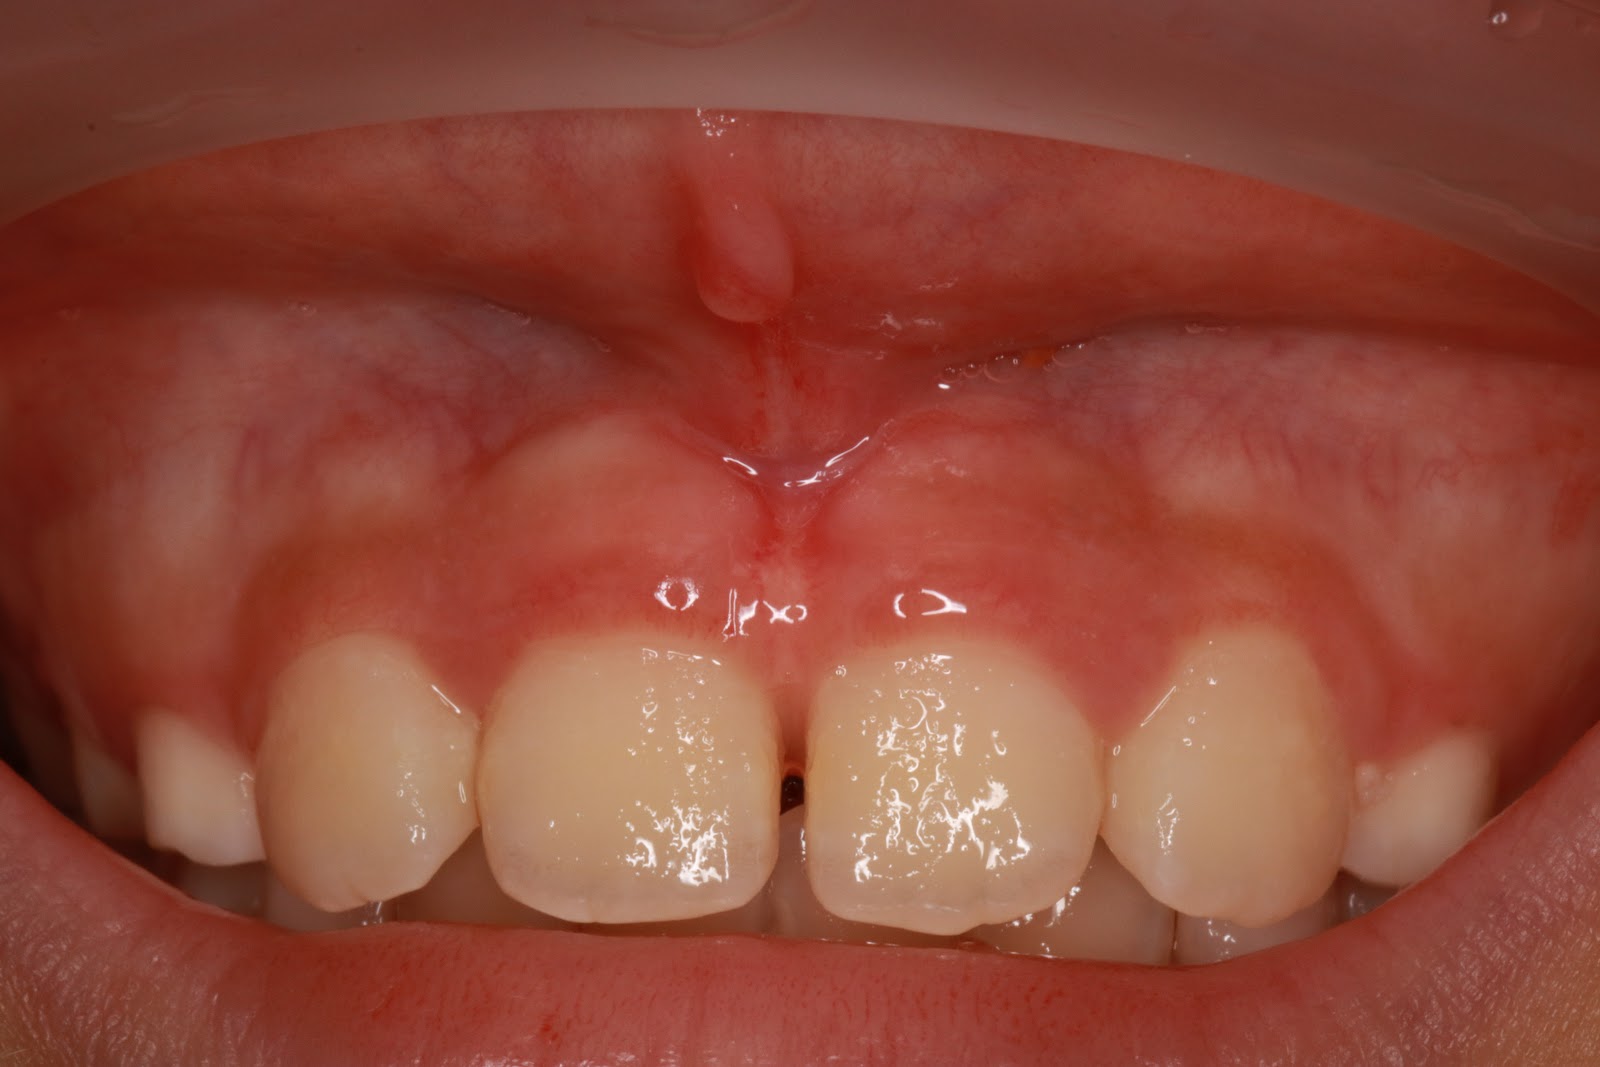

過長的唇繫帶

切除兩週後回診

前庭回復正常深度,且未影響附著牙齦寬度